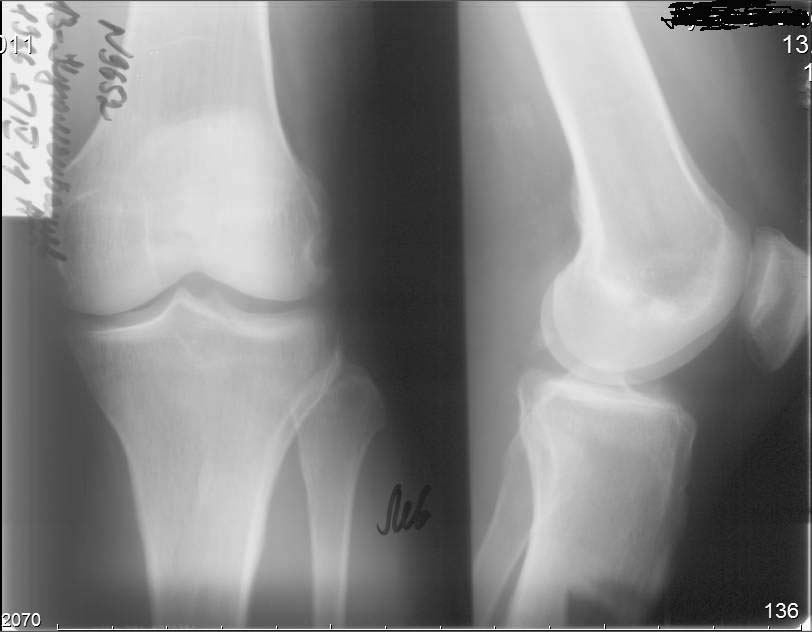

В настоящее время беспокоят боли в области правого надколенника, при длительной ходьбе появляется ощущение

скованности в 4-х главой мышце бедра, при отрыве правой стопы, голень и стопа как бы

выбрасывается вперед (пациент, при этом, процесс разгибания в коленном суставе плохо

контролирует). Правый коленный сустав внешне не деформирован, не отечен. Объем движений:

сгибание до 90 градусов (до прямого угла, разгибание полное_180 гр. Сустав стабилен во всех

плоскостях. Надколенник расположен практически на уровне суставной щели

(тибиа-феморальной), малоподвижен, так называемая ╚ игра надколенника ╩ у пациента резко

снижена .

Пациент поступил в наше отделение для выполнения операции в объеме

эндопротезирования правого коленного сустава. Однако, оценив коленный сустав, мы

засомневались в необходимости данной операции этому пациенту. В данном случае , низкое

стояние дегенеративно измененного правого надколенника нарушает функцию

разгибательного аппарата правого коленного сустава и основная причина сосредоточена

здесь, в надколеннике (по нашему мнению). У меня вопрос к коллегам: как деликатно, на нарушая

разгибательный аппарат, помочь пациенту? Какие виды реконструктивных операции

предпочтительны.